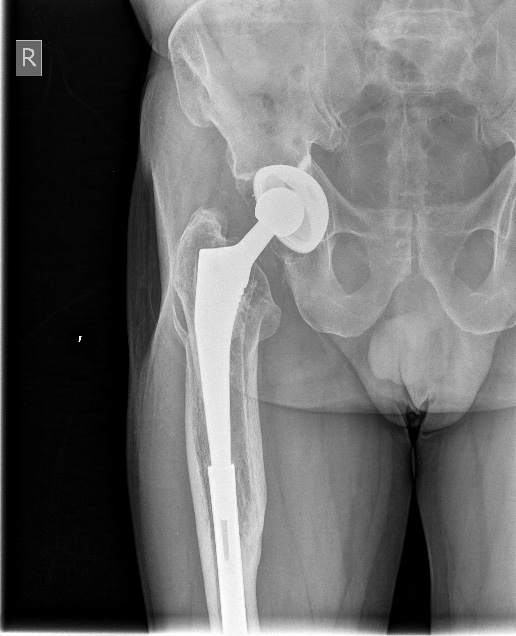

Закрытое штифтование с удлинением бесцементной ножки при переломах Vancouver B2/ B3 дает неожиданно для приверженцев традиционной догмы хорошие результаты.

Здесь первое наше наблюдение такого остеосинтеза с нестабильной ножкой. Прошло уже 6 лет - вот недавние снимки. Пациент не имеет жалоб, катается на коньках. Никакие дистальные винты не выдержали бы циклических нагрузок столько лет, если бы ножка оставалась нестабильной.

Как только увидел снимок, сразу промелькнула мысль - на старый гвоздь одеть новый ретроградный, именно это первым делом порекомендовал Шнеттлер. Отличные кейсы на этот счёт продемонстрировали Александр Николаевич и Алексей Юрьевич. По-моему, это очень даже reasonable вариант, учитывая аугментацию головки и остеопороз проксимального отдела.